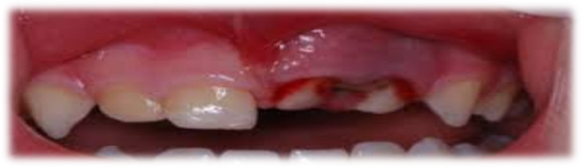

Ø What if tooth injured ,tooth broke or fall out due to sports activity or accident or any other reason?

Ø Must apply gentle pressure using clean cloth, gauze or cotton to control bleeding and immediately visit dentist.

Ø If tooth fall out ,try to place it back, avoid forcefully put it back in to socket. if you cannot put it back in socket ,place it in container of cold water ,milk

Ø Immediately contact dentist .

Ø બાળકોને રમતા રમતા આગળના દાંત ની ઈજા થાય કે પડી જાય તો તેની શું કાળજી લેવી?

Ø હળવા દબાણથી ચોખ્ખું કપડું રૂ દબાવી જલ્દીથી ડેન્ટિસ્ટ પાસે જવું જોઈએ.

Ø દાંત પડી ગયો હોય તો પાછું દબાણપૂર્વક મુકવાની કોશિશ ન કરવી ,આવા સમયે દાંતને ઠંડા પાણીમાં રાખી તાત્કાલિક ડેન્ટિસ્ટ નો સંપર્ક કરવો.